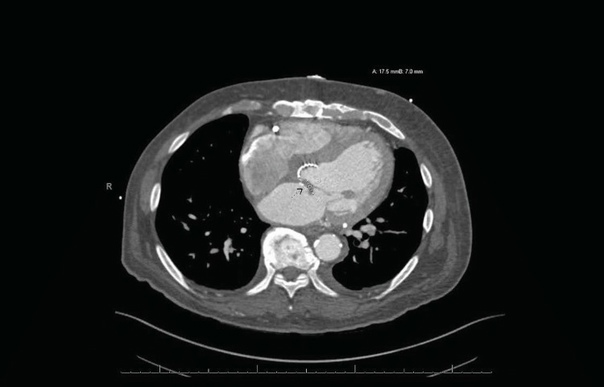

Жалобы на заложенность в ушах. Ранее у пациентки была выявлена ретркация барабанной перепонки, рекомендовано выполнять пользу Вальсальвы, что временно уменьшало ощущение заложенности.

В течение 6 лет пациентка выполняла упражнение 4 раза в день ежедневно.

При осмотре: в толще барабанных перепонок пузырьки воздуха, признаков отека или воспаления нет. Аудиография: умеренная кондуктивная тугоухость справа, нормальный слух слева.

Вероятнее всего изменения барабанных перепонок вызваны за счет частого выполнения пробы Вальсальвы.

Рекомендовано снизить интенсивность и частоту выполнения пробы.

При осмотре спустя 1 месяц отмечено улучшение.